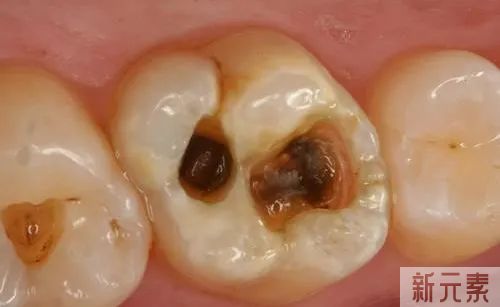

A: 通常蛀牙有三种阶段,肉眼可以直观,各位对号入座

第一阶段 :牙齿咬合面有黑线,大牙一般最常见,说明开始蛀牙了,牙釉质被细菌龋坏,但不痛不痒,会出现窝沟龋得及时补牙了,而不是去洗牙哦;

第二阶段 :牙齿出现小黑洞,说明引起中度蛀牙,细菌腐蚀来到牙本质,伴随着牙齿敏感,黑色腐败物质其实就是细菌的产物,这时候还可以再补牙;

第三阶段 :牙齿超过一半烂掉,说明已经重度蛀牙,细菌伤及牙髓牙神经,还伴随着剧烈疼痛,牙神经病变这时得需要根管治疗处理,挽救伤痕累累的牙齿。